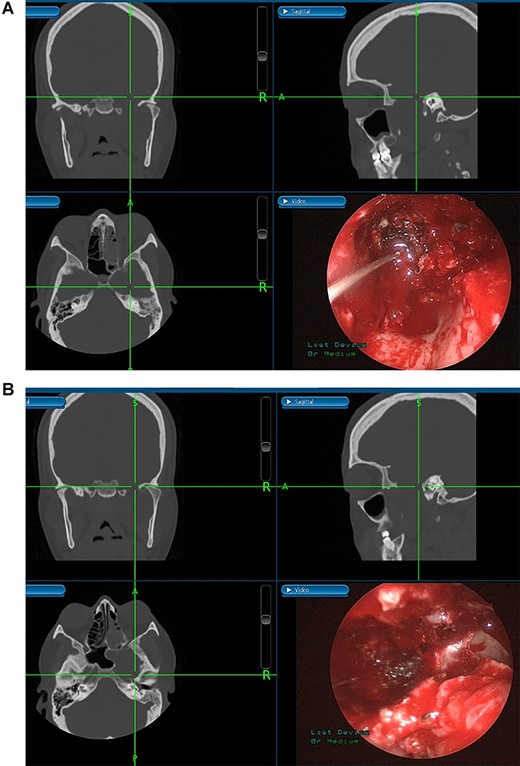

(A) Image-guided tumor removal from petrous carotid artery. (B) Image-guided intraoperative picture status post-complete tumor removal from trigeminal and middle cranial fossa.

The patient underwent an image-guided endonasal endoscopic tumor removal starting by endoscopic medial and posterior walls maxillectomies to control the tumor removal from the lateral sphenoid sinus and the infratemporal fossa after cauterization of the maxillary artery and sphenopalatine artery branches feeding the tumor. The tumor was dissected and removed from the cavernous (Fig. 3A) and petrous carotid artery in the middle cranial fossa (Fig. 3B). The middle cranial fossa’s dura was intact during the tumor removal (Fig. 3C). All the steps of tumor removal were controlled and monitored under image-guided navigation for accurate localization of tumor removal and avoidance of violation to the middle cranial fossa’s dura, or the brain, and the internal carotid artery in its cavernous and petrous segments (Fig. 4a and b).